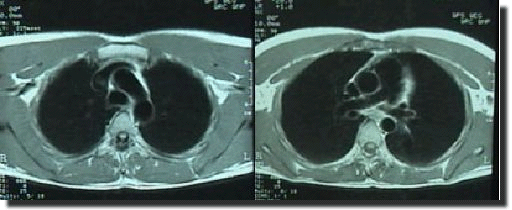

Slide B. axial T1 weighted sequence at D5 level

d. ascending aorta

e. descending aorta

f. main pulmonary trunk

g. right pulmonary artery

h. SVC

i. left bronchus